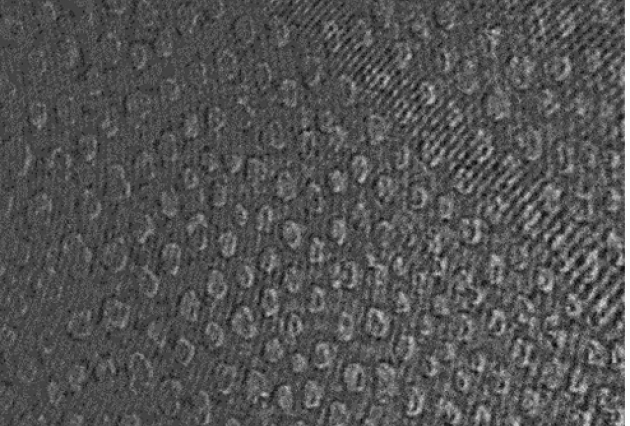

Publié le 03/08/2017Une membrane-modèle pour étudier l’effet de l’amoxicilline sur les cellules

L’amoxicilline (AMX) est un antibiotique dont le mécanisme d’action favorise la lyse et ainsi la mort de certains types de bactéries. L’AMX est le traitement classique pour lutter contre différentes (...)Lire la suite -

Publié le 03/08/2017Une membrane-modèle pour étudier l’effet de l’amoxicilline sur les cellules

L’amoxicilline (AMX) est un antibiotique dont le mécanisme d’action favorise la lyse et ainsi la mort de certains types de bactéries. L’AMX est le traitement classique pour lutter contre différentes (...)Lire la suite -